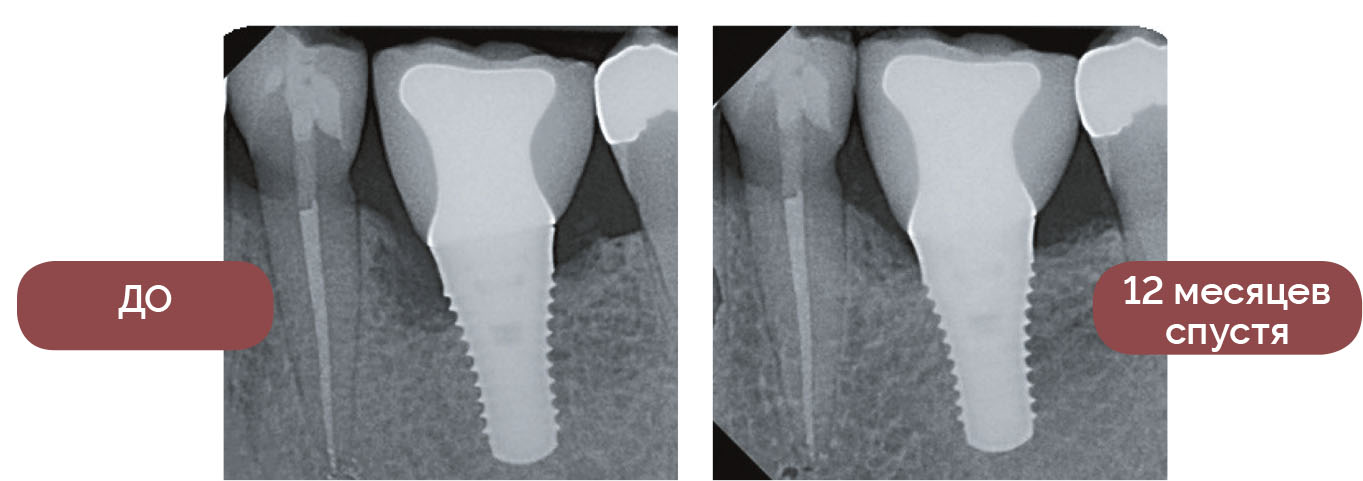

Польза от использования лазера Waterlase iPlus подтверждена уникальным клиническим исследованием в области пародонтологии, соответствующим строгим стандартам AAP Best Evidence Consensus, опубликованным в Journal of Periodontology.

РЕЗУЛЬТАТ: минимально инвазивные протоколы Waterlase REPAIR™ получили не только положительные отзывы пациентов (меньше отеков, гематом и кровоточивости), но и показали более короткое время проведения процедур при клинической эффективности, сопоставимой с современными методами открытых разрезов.